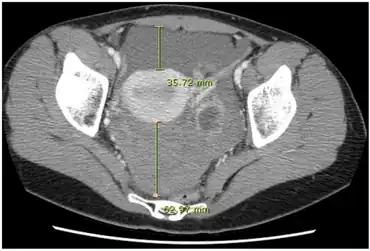

CT quantification of hemoperitoneum. | |